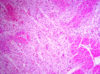

Organizing myocardial infarct

Macroscopy of:

- Old infarct:*

- Acute infarct:*

- 2nd week:*

- Old infarct* – fibrosis – white (granulation tissue)

- Acute infarct* – dark yellow mottling

- 2nd week* – collagen fibers deposit, scar formation begins